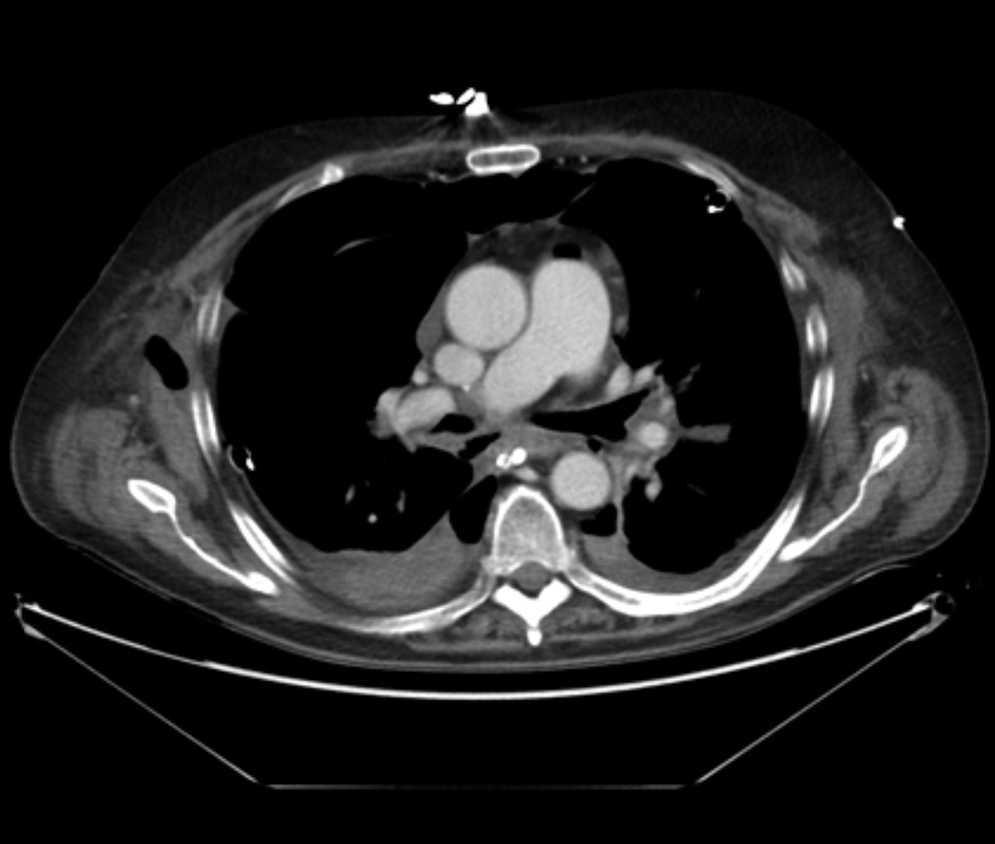

Pulmonary vein obstruction is usually an early complication, occurring during the first few hours after transplantation, and causes severe symptoms. Marked hypoxia, pulmonary edema, and pulmonary infiltrates are observed. If the lower lobe is more severely affected, a high suspicion for such a complication is warranted, and an early additional diagnostic test should be ordered. The initial test should be a transthoracic or transesophageal echocardiogram, in spite of this test being only useful for diagnosis when performed by an experienced operator, due to a challenging visualization and interpretation after recent surgery 6. Alternatively, chest CT angiography can be used, which also allows artery suture and distal vascularization to be assessed and reconstructions to be produced. CT angiography establishes the diagnosis in most cases. Anticoagulation using heparin and clinical course monitoring is used to manage partial thromboses and stenoses. In the event of a complete vein obstruction or a poor course, in patients with a very recent surgery, re-transplantation or lobectomy for double-lung transplantations, may be needed. If the patient is in a stable condition, several days have elapsed, and anatomic characteristics are favorable, an angioplasty with dilation and stent implant can be considered.

Arterial suture complications are usually less common and are found later. They result in persistent hypoxia and pulmonary hypertension. Diagnosis is based on CT angiography and/or arteriography. Some degree of arterial suture stenosis with no clinical significance is commonly found in CT angiography, due to donor-receptor size discordance or to the suture itself. Significant stenoses are due to kinking or thrombosis at the suture level. The former are usually treated win angioplasty and dilation, whereas usual therapy for the latter is stent implant if required. Anticoagulation is used for thrombotic cases 7.

Figure 3. Coronal view in CT angiography showing complete lower pulmonary vein obstruction after left lung transplantation.

Figure 4. CT image showing extensive lung infiltrates in lower left lobe resulting from lower pulmonary vein obstruction.